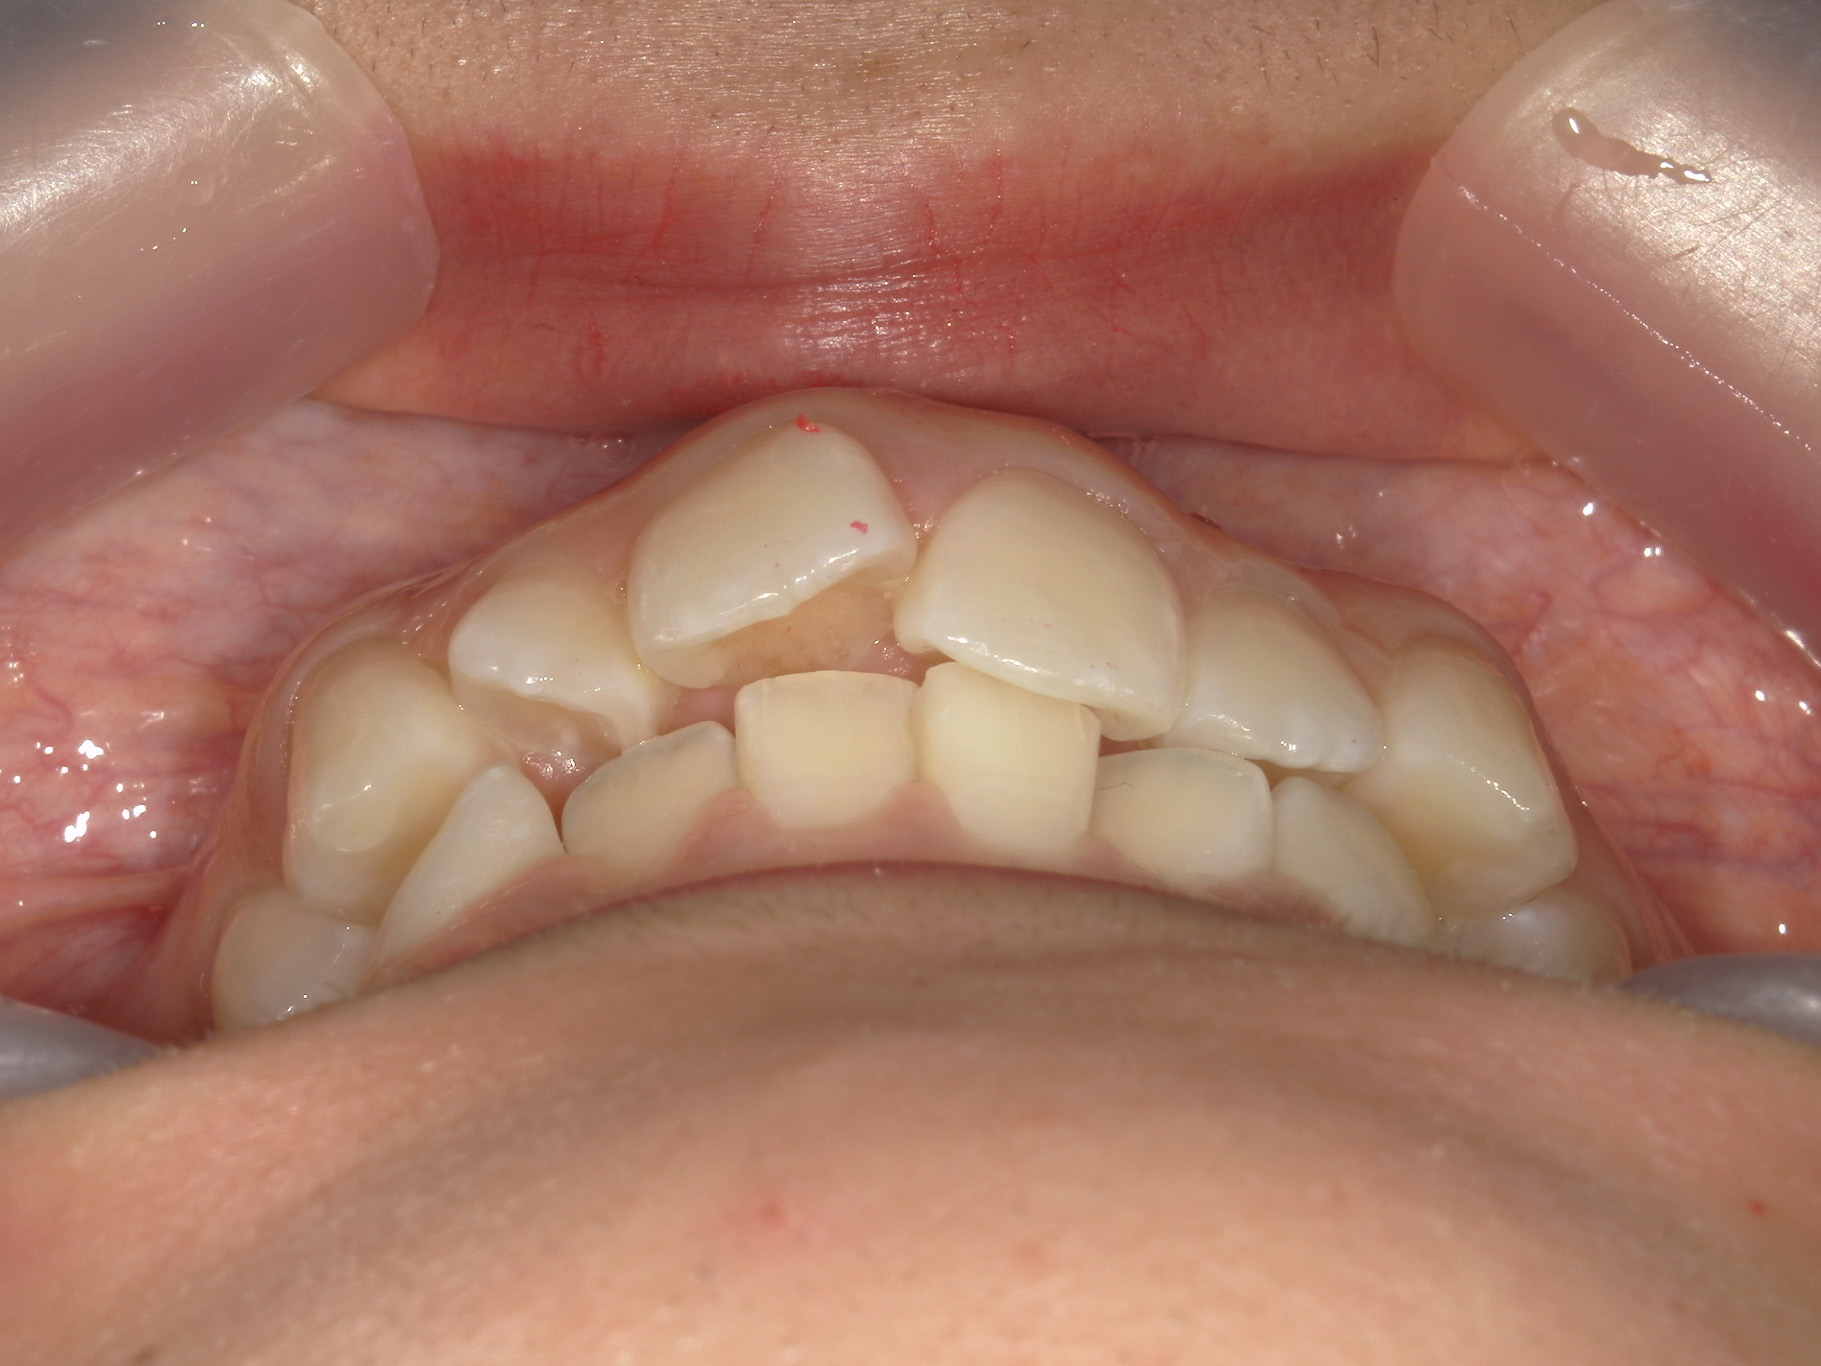

プチワイヤー矯正 症例(54)

主訴: 歯並びが気になる。

カテゴリー : ガタガタ(叢生)